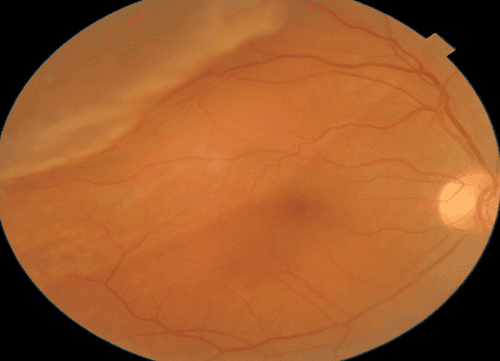

Figure 1: Macula-splitting rhegmatogenous retinal detachment OD shown in 62 y/o female. This patient had visual symptoms of flashing lights and shadows for almost eight weeks before presenting for evaluation. Patients with pre-operative macula-off status are over three times as likely to experience postoperative symptoms of metamorphopsia. Photo courtesy of Kevin Cornwell, OD